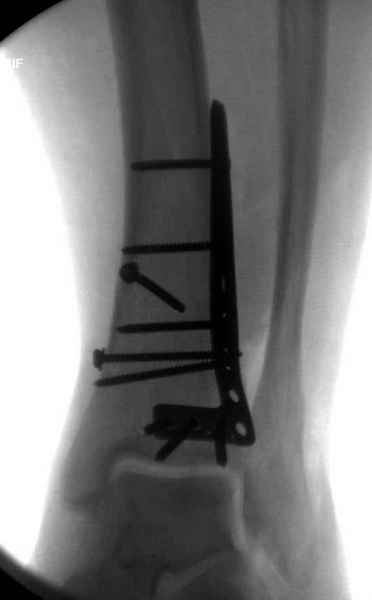

В приложении метафизарный перелом у ребёнка 14лет, с распространением линии перелома на зону роста.

В примере показан не перелом пилона, а эпифизеолиз, м/берцовую кость сознательно не фиксировал(длина её восстановлена, ротации нет),у детей стараемся минимизировать операц.травму, несколько позже разрешил полную нагрузку на ногу(4 недели). Но принцип фиксации б/берцовой кости м.б. таким же.